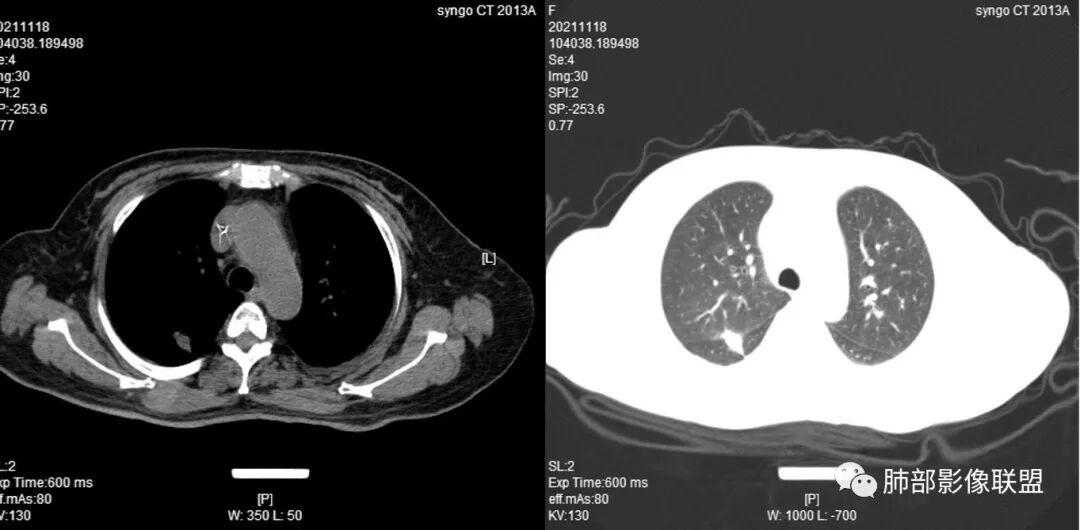

4.白血病化疗后,CT上出现多发结节,边缘可见晕征,病灶内可见多发坏死,右肺中叶肺动脉可见充盈缺损,右肺中叶可见融冰征,右肺中叶肺动脉侵犯栓塞伴右肺中叶肺梗死,可符合真菌感染。

血管侵袭性曲霉病是最常见的类型,其特征是真菌菌丝侵入和阻塞中小肺动脉,形成凝固性坏死、肺泡出血或出血性梗死。

6.肺曲霉病典型的CT表现是结节周围有磨玻璃样的晕征表现,或胸膜为宽基底的楔形实变。晕征表现为曲菌感染的肺结节伴梗死和凝固性坏死,周围有肺泡出血。最终可出现空泡征象,并可观察到中央坏死组织与周围肺实质分离形成空气新月征。

晕征已被认为是侵袭性曲菌病的早期征象之一。